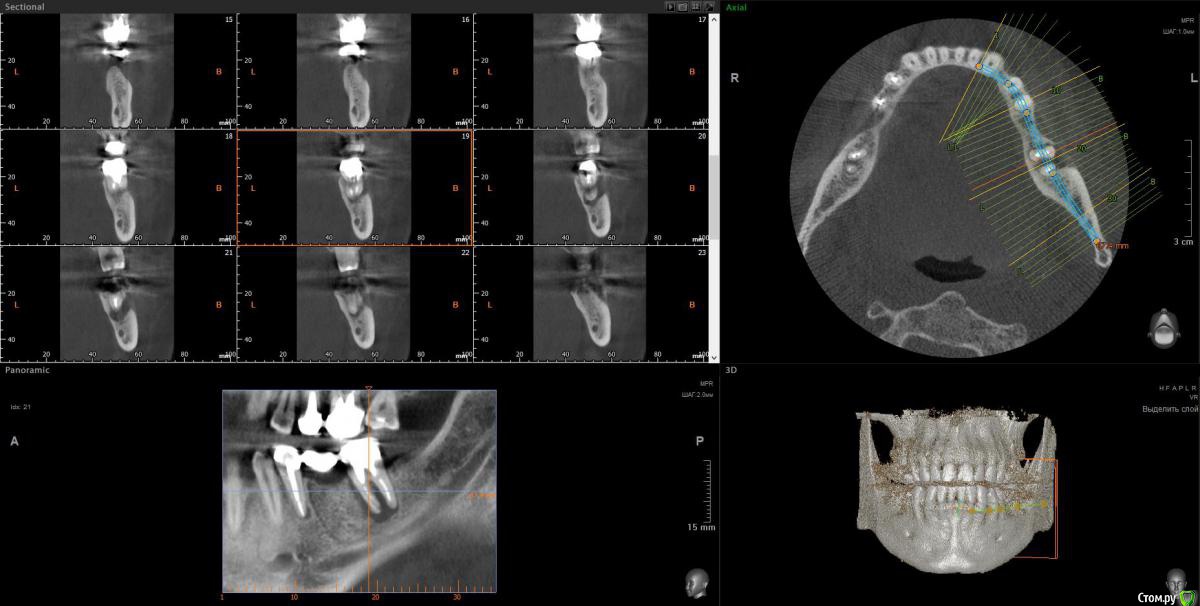

Taurus007 Опубликовано 9 февраля, 2018 Поделиться Опубликовано 9 февраля, 2018 После очных консультаций в разных клиниках (Москва) выяснилось много вариантов, что несколько смущает. Рекомендации и планы лечений такие:1.Удалить 15,16.25,26,37,47 . С учетом ранее удаленных 2х нижних шестерок, поставить 8 имплантов.При необходимости - подсадка костной ткани.2.Удалить 46,47,36,37,16,26, на их место импланты. 15,25 - поменять коронки. Дополнительно: а. Синус-лифтинг в различных комбинациях, либо без него. Мнения разные. б. Высказано мнение, что необходима коррекция прикуса, поскольку если его не трогать, а начать установку имплантов, то нагрузка на них будет чрезмерной, что повлечет рассасывание кости со всеми вытекающими. Сделал ТРГ, пока только снимок, анализ и расчет ТРГ на след. неделе будет готов. Из истории зубов: коронки стоят 9 лет, 35й - 1 год. Ссылки на ТРГ и компьютерную томографию . Сам я изначально склонялся к первому варианту. Без исправления прикуса.Подскажите, как все-таки лучше поступить? Важные вопросы: насколько необходимо исправление прикуса, и нужен ли синус-лифтинг, судя по КТ? Ссылка на комментарий

red_butler Опубликовано 9 февраля, 2018 Поделиться Опубликовано 9 февраля, 2018 насколько необходимо исправление прикуса для ответов нужно больше информации - http://forum.stom.ru/topic/4655-patcientam/ и нужен ли синус-лифтинг, судя по КТ? Выкладывайте срезы Кт, весь архив мало кто станет/сможет качать. 1 Ссылка на комментарий

wladdX Опубликовано 12 февраля, 2018 Поделиться Опубликовано 12 февраля, 2018 Скрины 1 Ссылка на комментарий

Bier Опубликовано 22 февраля, 2018 Поделиться Опубликовано 22 февраля, 2018 Справа синуслифтинг не потребуется 100%Слева - возможно в области 26 зуба. Для оценки прикуса одного ТРГ мало, надо еще фото моделей. Вам их наверное делали? Ссылка на комментарий

Taurus007 Опубликовано 24 февраля, 2018 Автор Поделиться Опубликовано 24 февраля, 2018 Справа синуслифтинг не потребуется 100% Слева - возможно в области 26 зуба. А в целом, можно ли сейчас не трогать область, где возможно потребуется синуслифтинг, поскольку в практическом смысле это наименее проблемная область, хоть коронки и стоят уже 9 лет ? надо еще фото моделей. Вам их наверное делали? Не делали. Это как-то в домашних условиях возможно? Ссылка на комментарий